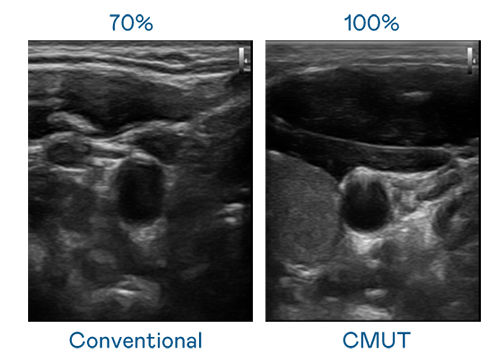

CMUT 技术是一种用电容式微机电元件来产生超音波讯号的技术。与传统 PZT 压电式技术相比,CMUT 频宽增加 30%,更宽频的超音波讯号让影像解析度大幅提升,是实现高影像品质医疗超音波扫描、促进精准医疗发展的关键技术。

大频宽带来超清晰影像

超音波影像的解析度高低,首先取决于探头能发出的讯号频宽。恒峰g22 CMUT 可提供高清晰的超音波讯号,提供高频宽、高灵敏度、影像纹理细节更高的超音波影像,协助医护人员缩短影像判读时间及利用精准的医疗影像进行诊断。